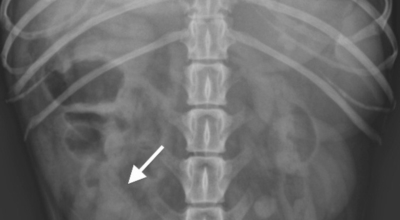

흉추와 복장뼈를 관련해서 가슴 전체를 둘러싸고 있는 가슴우리(흉강)을 형성하는 긴 곡선의 뼈를 말합니다. 갈비뼈는 폐, 심장 등 내부 가슴 장기들을 지켜주며 가슴우리의 팽창과 수축으로 호흡을 도와줍니다. 우리 몸은 총 12쌍의 갈비뼈를 가지고 있답니다.

1~7번 갈비뼈는 복장뼈와 직접 관절로 연결되어 있어 참갈비뼈라고 하며, 8~12번 갈비뼈는 거짓 갈비뼈라고 하는데 거짓 갈비뼈 중 8, 9, 10번 갈비뼈는 또다른 연골을 통해 복장뼈와 연결되어 있으며 나머지 11~12번째 갈비뼈는 뜬갈비뼈로 복장뼈와 연결되어 있지 않습니다.